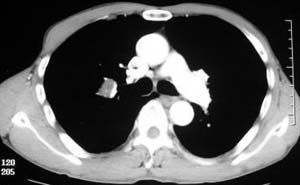

患者,男,58岁,煤矿职工,无症状,单位体检发现病变。

右肺门上缘见类圆形节结影,密度尚均,边缘清楚,其内可见点状钙化影,周围支气管受压移位,病灶未见明显强化。考虑:1炎性假瘤  2 支持周围型肺ca (腺瘤)

右肺门上缘见类圆形节结影,密度尚均,边缘清楚,其内可见点状钙化影,周围支气管受压移位,病灶未见明显强化。考虑:良性病变——结核球可能性大,周围型肺癌待排。

病灶边缘光滑,似可见分叶征,未见明显毛刺。气管影轻度向右偏移。内可见点样钙化。邻近气道影通畅,考虑结核球可能。请楼主尽快公布结果

病灶呈分叶型,边缘清晰,无毛刺,增强强化不明显,内见多发钙化,亦无卫星灶。多考虑良性病变。错构瘤可能性大。

病灶呈分叶型,边缘清晰,无毛刺,增强强化不明显,内见多发钙化,亦无卫星灶。多考虑良性病变。错构瘤可能性大或结核球。肺癌待排

动脉相上,右上肺动脉的尖段分支位于结节旁,结节对血管形成压迫而使到走行略改变,并没有很明确的包绕,也没有动脉期的供血,考虑还是偏向于良性可能大。当然最后的决定还是病检

病变边界清晰,对周围主要是外压性改变,未见血管包绕,边缘及中心见钙化,考虑良性病变,结核球可能